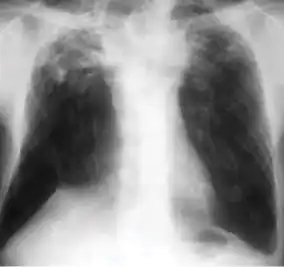

In active pulmonary TB, infiltrates or consolidations and/or cavities are often seen in the upper lungs with or without mediastinal or hilar lymphadenopathy.[1] However, lesions may appear anywhere in the lungs. In HIV and other immunosuppressed persons, any abnormality may indicate TB or the chest X-ray may even appear entirely normal.[1]

Old healed tuberculosis usually presents as pulmonary nodules in the hilar area or upper lobes, with or without fibrotic scars and volume loss.[1] Bronchiectasis and pleural scarring may be present.

Abnormalities on chest radiographs may be suggestive of, but are never diagnostic of, TB.[1] However, if a person has a positive response to the tuberculin skin test and no symptoms of the disease, chest radiographs can be used to rule out the possibility of pulmonary TB.